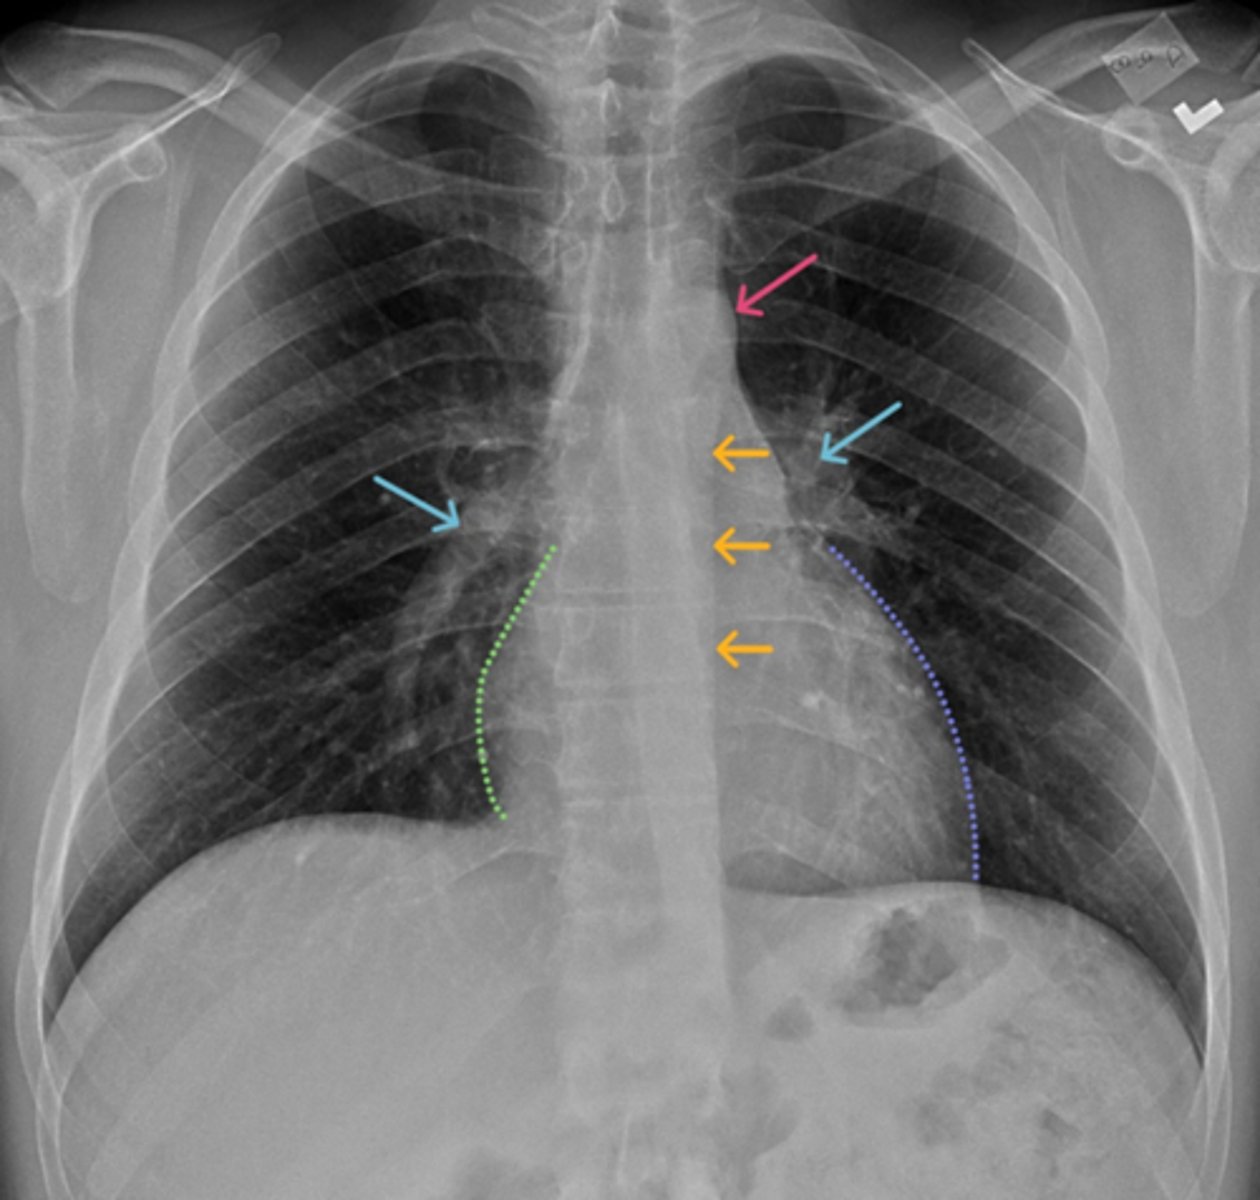

Aortic knob/arch

Pink Arrow

Left ventricle and border of the heart

Purple Line

Pulmonary arteries

Blue Arrows